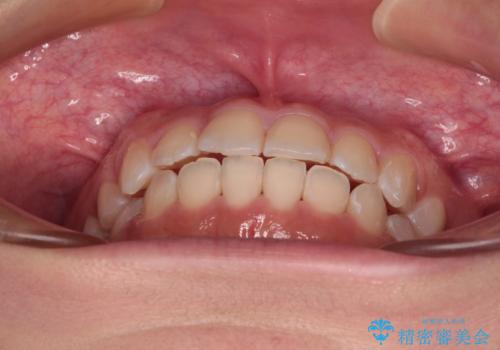

- 前歯のデコボコを気にして来院された患者様です。

マウスピース矯正のような自己管理の煩わしさがなく、早く治療を終えたいとのことで、ワイヤー装置による矯正治療を行うこととしました。

当初予定通り、1年で治療を終えることができました。